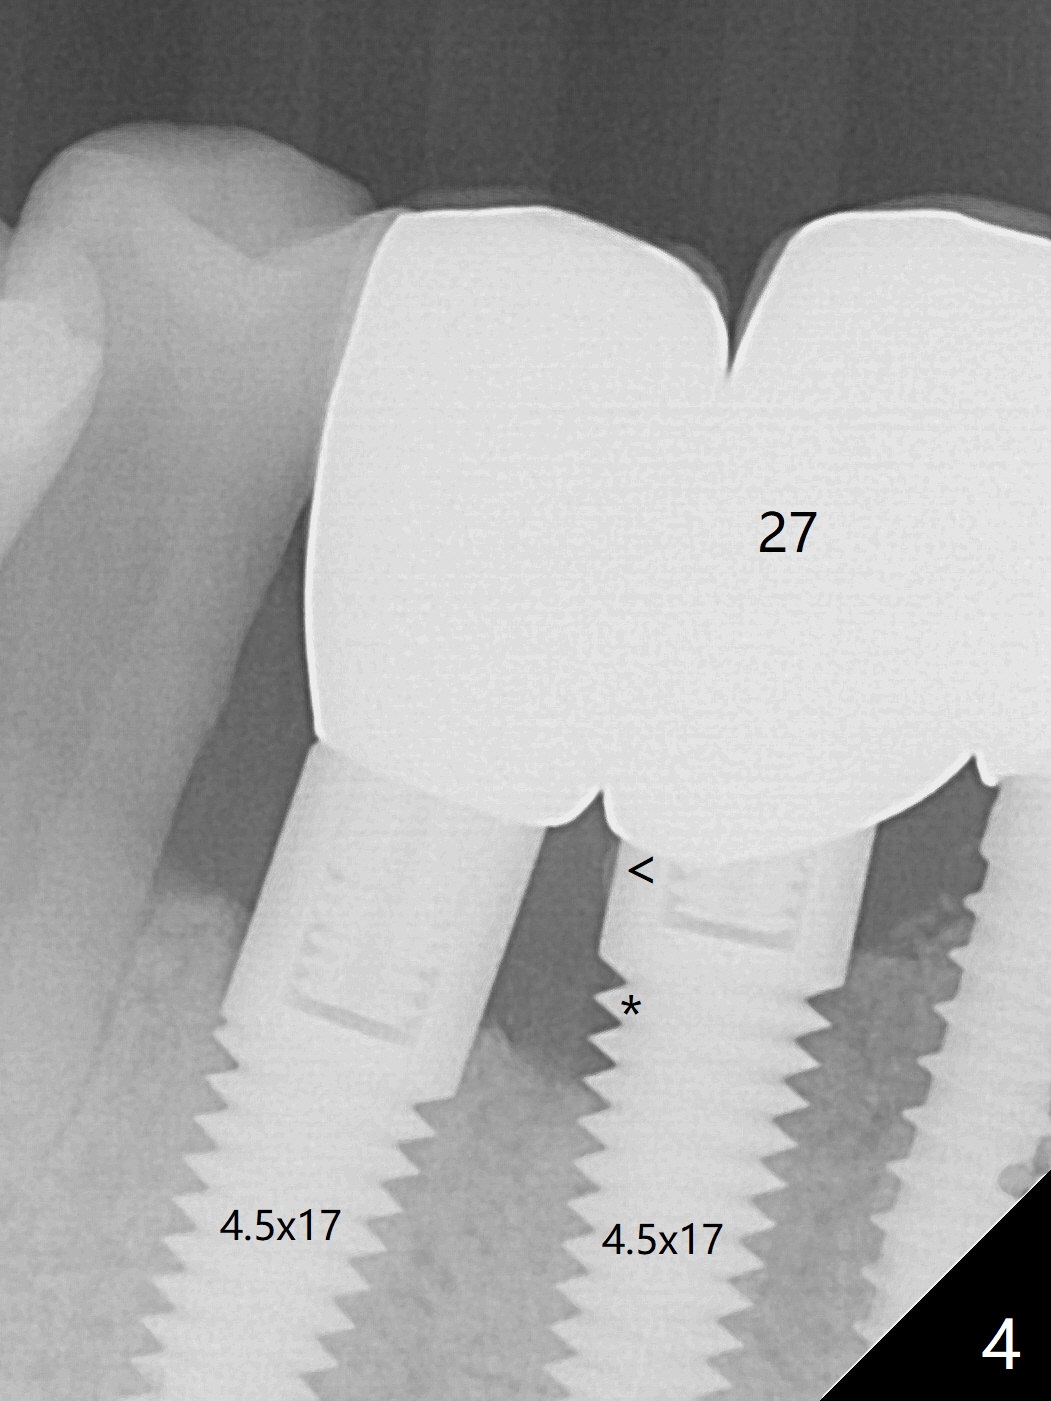

A 67-year-old man with history of chronic periodontitis and bruxism returns to clinic requesting implant for the tooth #20 with mobility (Fig.1). To assure No Deviation of implant placement, Lindamann bur will be used to remove the most coronal of the buccal aspect (Fig.2 *, 3 pink dashed line) of the thick lingual plate (L) during osteotomy. To reduce bone loss (Fig.4 *) associated with residual cement (Fig.4,5 arrowheads) of the tissue-level implants, a bone-level one (SM) will be used at #20. Check whether the nearby implant (#19) has infection clinically and bone graft if needed. Buccolingual threads of the #27 implant are also exposed 3 years 9 months post cementation (Fig.6). An ideal treatment is probably to remove the 4.5x17 mm tissue-level implant and place a 3.8x10 mm bone-level one deeper and a little mesial with bone graft.